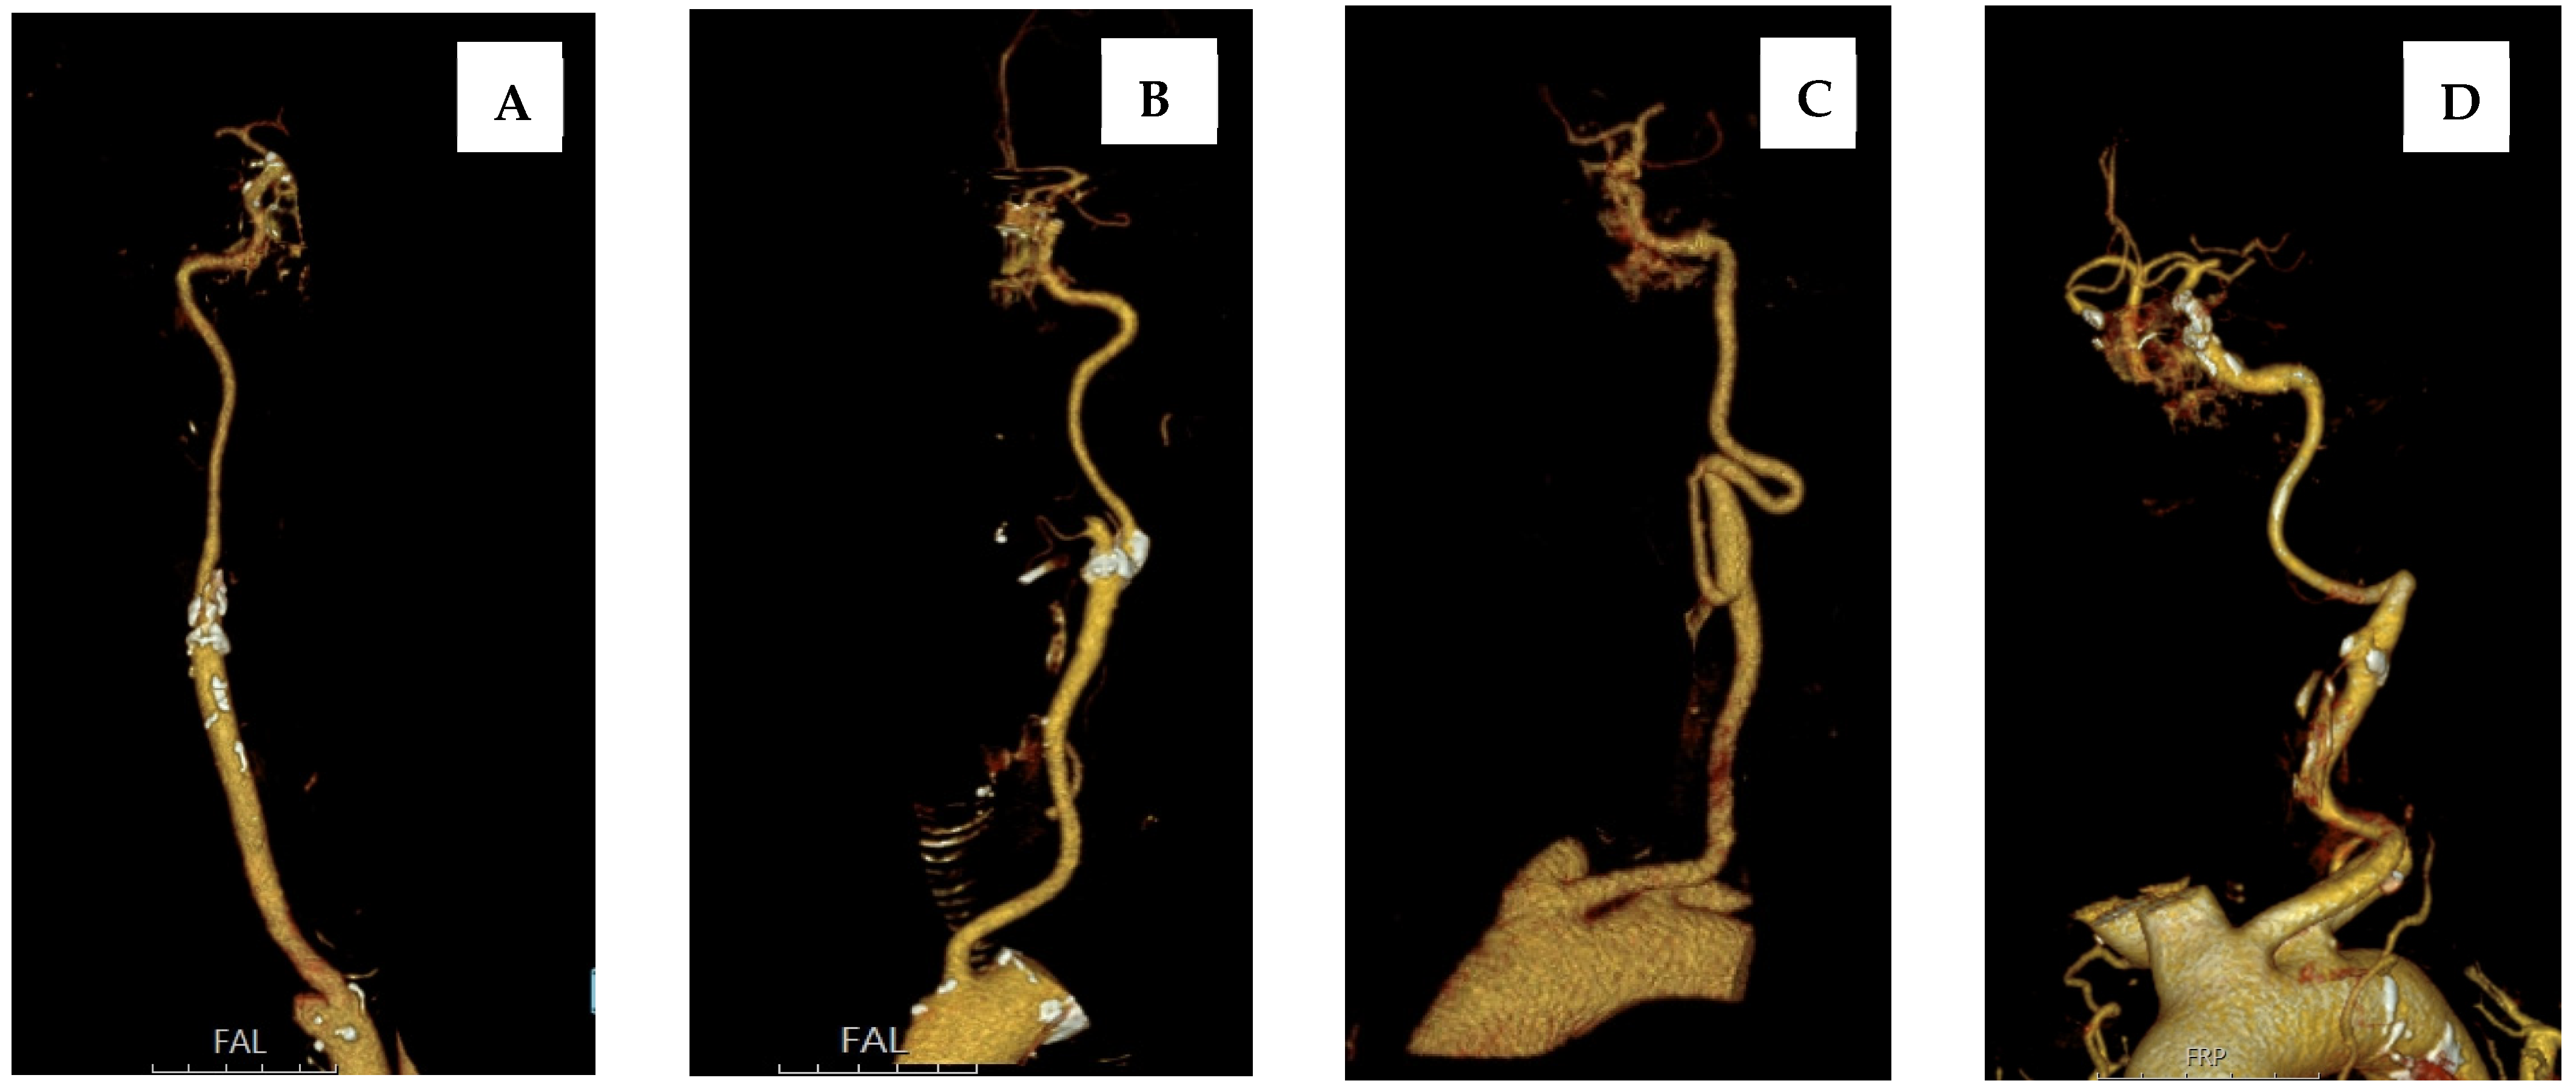

2.2. Arterial Tortuosity Measurement and Definition